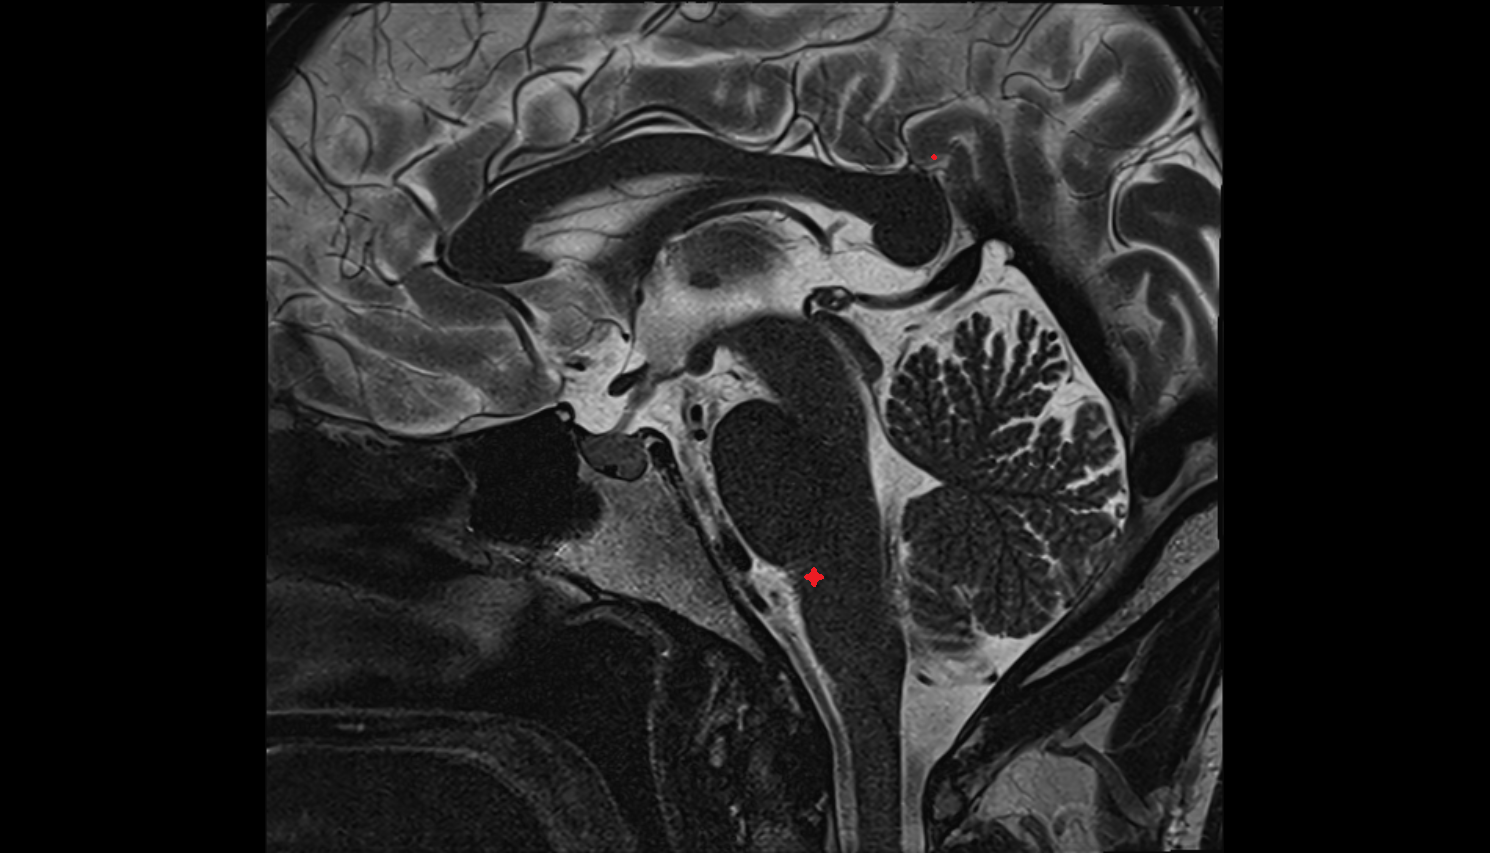

- Aqueduct of midbrain (Sylvian Aqueduct)

- Pons

- Fourth ventricle

- Median aperture of fourth ventricle (foramen of Magendie)

- Cerebral aqueduct